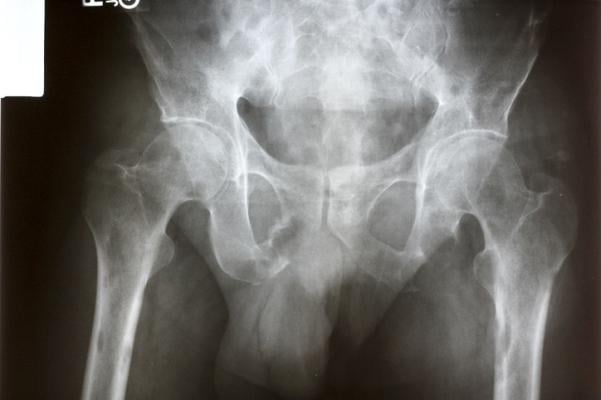

For the study, researchers identified 78 adults with a metastatic solid tumor malignancy and more than five metastatic lesions, including at least one asymptomatic high-risk bone lesion. Whether a lesion was high-risk was determined by its size (if it was 2 centimeters or more in diameter); its location in the junctional spine; whether it involved the hip or sacroiliac joint; or if it was in one of the long bones of the body, such as those found in arms and legs. Between all enrolled patients, there were a cumulative 122 bone metastases.

The primary endpoint was to determine whether treating asymptomatic lesions could prevent skeletal-related events (SREs) – a common and often painful and debilitating complication of bone metastases. SREs include pain, fractures and compression of the spinal cord that requires surgery or radiation. They can contribute to a higher risk of death and higher health care costs.

Researchers found that treating the asymptomatic lesions with radiation reduced the number SREs and SRE-related hospitalizations and extended overall survival, compared to people who received no radiation. At the end of one year, for patients on the radiation arm, SREs occurred in 1 of 62 lesions (1.6%), compared to 14 of 49 lesions (29%) for those receiving standard care (p<0.001). Significantly fewer patients in the radiation arm were hospitalized for SREs (0 vs. 4, p=0.045).

Though it was not in the initial study design, Dr. Gillespie said the team performed an unplanned analysis of which lesions were most likely to cause SREs. While they expected to find those in the long bones might cause more fractures and pain, they found it was metastases in the spine that were most likely to cause subsequent pain, cord compression or fracture. However, the numbers are small and will require further evaluation to confirm.